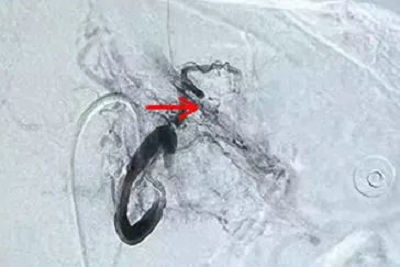

▲ 胃左动脉动脉瘤破裂出血

吕军主任带领的介入科团队在书中精细操作,导管与导丝到位,高压造影显示杂乱的胃左动脉远端合并胃动脉瘤,颗粒栓塞胃左动脉远端保留主干,当即李大爷既感觉胃部不适感减轻,血压回升,心率也平稳了下来。术后返回介入科病房观察治疗,在护士长李凌乐带领的护理团队精心照顾下,目前李大爷已恢复如常,近期在胃镜室的帮助下已完成胃部肿瘤活检考虑为胃腺癌,现已转专科行手术治疗。